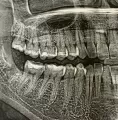

Мне удалили нижнюю восьмерку. Удаление было сложное. Зуб давил на 7-ку, произошло скучиванье нижних зубов. Удаляли 1,5 часа, 2 раза обезболивали, потом накладывали швы.

Операция происходила 13 сентября, сегодня уже 30, а рот открывается только на размер указательного пальца. Иногда там болит, но по виду все заживает. При попытке открыть рот шире, жуткая боль в том месте, где удаляли.